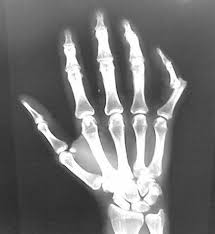

Apply an ice pack to your injured finger and elevate the hand above the level of your heart. Continue elevating your finger when possible. Sometimes, relocating a finger dislocation can be simple and other times it can be very difficult. When a joint is dislocated, the normal alignment of the finger is altered, and the joint must be put back into place. In these challenging situations, there may be tendons or other tissues preventing the joint from going back into position.

There is a broad spectrum of severity of finger ligament injuries, and therefore having these evaluated by your doctor can help ensure that you are not avoiding necessary treatment. A dislocated finger won't move because. In some cases, the damage to the supporting ligaments is significant enough that the joint comes apart, causing an injury called a dislocation. See full list on verywellhealth.com Ice the finger for 20 minutes every few hours for a few days, if you are able.

Thumb sprains and certain finger sprains in children may require a longer period of immobilization or evaluation by a specialist, especially if there is concern that a ligament was torn. To prevent further injury to the finger, immediately remove any. Treatment of a dislocated finger is similar to that of a sprained finger. A dislocated finger won't move because. Remove any jewelry from your dislocated finger. What will happen to my dislocated finger? In this video we demonstrate a metacarpal block and the reduction of a dislocated fifth finger. That said, most finger dislocations can be treated with a simple splint. What is the recovery time for a dislocated finger? You should discuss with your doctor when to begin finger movements. Great exercises that help.in this video i am going to go over so. See full list on verywellhealth.com A finger dislocation is a more severe injury to the digit, as it involves not only the ligament, but also the surrounding joint capsule, cartilage, and other tissues.

How do i treat a dislocated finger? Usually, you'll be able to use your hand as normal within a week, but don't worry if a sprain causes pain and discomfort for a longer period of timethat's normal. Although a dislocation is a more serious injury, expect treatment similar to that of a sprain. When a sprain occurs, a ligament that supports a joint is stretched too far and the tough fibers of the ligament tissue become either partially or completely torn. Other treatments for a sprained finger include: There is a broad spectrum of severity of finger ligament injuries, and therefore having these evaluated by your doctor can help ensure that you are not avoiding necessary treatment. In some cases, the damage to the supporting ligaments is significant enough that the joint comes apart, causing an injury called a dislocation. Other times, the dislocation may require anesthesia or even a surgical procedure to realign the digit. Finger dislocation treatment if you have a dislocated finger, the finger will swell. Once the joint has been put back into position, the finger is splinted to allow the ligaments and joint capsule to heal. In addition to a splint, or sometimes instead of a splint, your doctor may use medical tape to bind your injured finger to an uninjured one next to it. Continue elevating your finger when possible. Remove any jewelry from your dislocated finger.